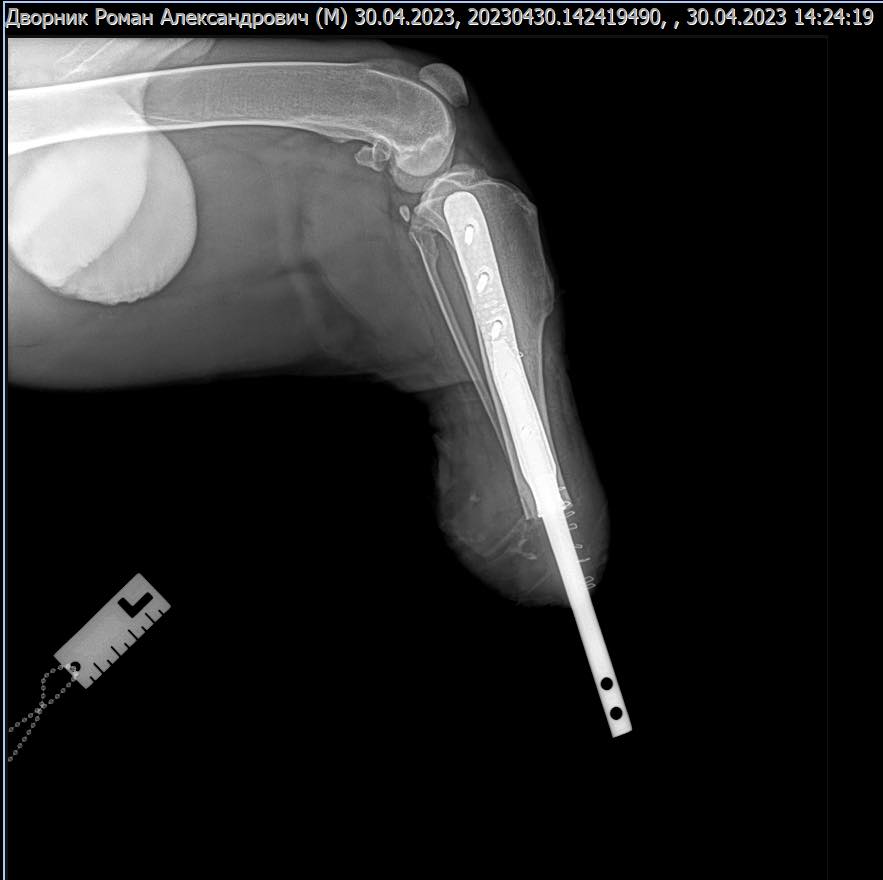

На базі Салтівської ветеринарної клініки – філії легендарного Харківського ветеринарного шпиталю зробили складну операцію тер'єру. Собаці вживили біоінтегрований протез. Подібних операцій у Харкові ще не робили.

Пес залишився без лапи внаслідок російського бомбардування.

"Хотів представити перше в Харкові біоінтегроване протезування кінцівки у собаки та ще вагою 56 кг. Операцію виконано на базі Салтівської ветеринарної клініки філія легендарного "Харківського ветеринарного госпіталю". Травматична ампутація кінцівки через бомбардування російськими окупантами, забороненими касетними снарядами в Харківській області. Чорний тер'єр потрапив під обстріл у садку. Сподіваємось на швидке одужання нашого пацієнта. Подяка власникам, які не кинули свого улюбленця у такі скрутні часи. Коли вони розповідали, як його пораненого переправляли через лінію фронту, кров стане у жилах. Розробка імпланту 3D metal tech!" – розповів у Фейсбуці головний лікар Харківського ветеринарного госпіталю Віталій Клубань.